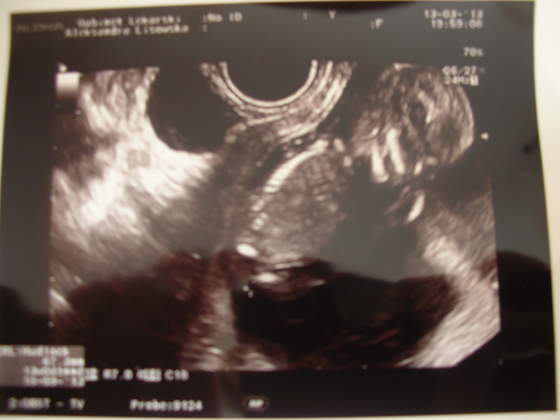

"Zmolestowałam" moją Panią doktor, żeby "skoro już tu jestem" zrobiła mi usg - tak na uspokojenie nerwów chciałam zobaczyć, że serduszko puka. Pani doktor się zgodziła (pomimo iż już miała 30 min opóźnienie w kolejce, a formalnie wskazań nie było, bo widziałyśmy się niedawno i brak krwawień, itp). Podpatrzyłam sobie bobaska, a pani doktor przy okazji wymierzyła wszystko dokładnie (i tak chcąc, nie chcąc trafiłam przypadkiem na badanie przesiewowe, "bo skoro już tu jestem" ;-)). Wszystko w normie, bobasa podpatrzyłam z wszystkich możliwych stron i wyszłam z gabinetu bogatsza o dwa zdjęcia:

Według usg bobas ma 67 mm, czyli 13t0d oraz termin 18.09.2013.